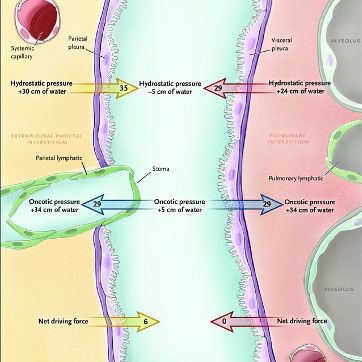

7/In pleural malignancy, there is an  https://abs.twimg.com/emoji/v2/... draggable="false" alt="⬆️" title="Pfeil nach oben" aria-label="Emoji: Pfeil nach oben">in capillary leakiness with

https://abs.twimg.com/emoji/v2/... draggable="false" alt="⬆️" title="Pfeil nach oben" aria-label="Emoji: Pfeil nach oben">in capillary leakiness with  https://abs.twimg.com/emoji/v2/... draggable="false" alt="⬇️" title="Pfeil nach unten" aria-label="Emoji: Pfeil nach unten"> clearance by the lymphatics located on the parietal pleura due to malignant infiltration. Fluid will continue to accumulate until there is an equilibrium of oncotic and hydrostatic pressures across the pleura.

https://abs.twimg.com/emoji/v2/... draggable="false" alt="⬇️" title="Pfeil nach unten" aria-label="Emoji: Pfeil nach unten"> clearance by the lymphatics located on the parietal pleura due to malignant infiltration. Fluid will continue to accumulate until there is an equilibrium of oncotic and hydrostatic pressures across the pleura.

12/In trapped lung, the fibrotic process affecting the visceral pleura causes an increase in the negative pleural pressure resulting in fluid accumulation and reduction in the removal of fluid by pleural lymphatics. @UpToDate @gsmartinmd @jackpenner